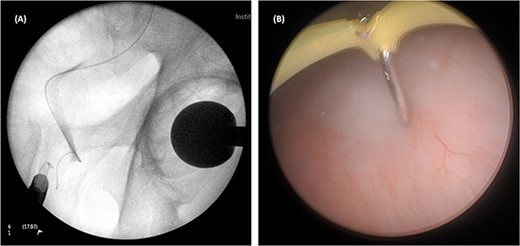

On both cases, under general or regional anaesthesia, a cystoscopy was performed and the interureteric bar was identified. A hybrid ‘sensor’ or ‘Terumo’ hydrophilic guidewire was advanced concurrently using the access from the existing nephrostomy tube with fluoroscopic assistance down to the level of the ureteric cul-de-sac. A combined visual- and x-ray-guided approach verified the exact location of the course of the intramural ureter, in correlation to the resectoscope and a Collins knife was used to incise the bladder mucosa (Fig. 2) above the level of the guidewire, on the virtual course of the intramural ureter exposing the intramural ureter. In all three attempts, the incision of bladder mucosa above the antegrade ureteric guidewire ended up with a successful identification of the guidewire, allowing access to the ureteric cul-de-sac. Stent graspers were used to snare the guidewire into the bladder (Fig. 3). With safety wire in place, management of the neo-orifice could then be performed.

A combined visual- and x-ray-guided approach verified the exact location of the course of the intravesical intramural right ureter, in correlation to the resectoscope. (A) X-ray, (B) cystoscopic view.